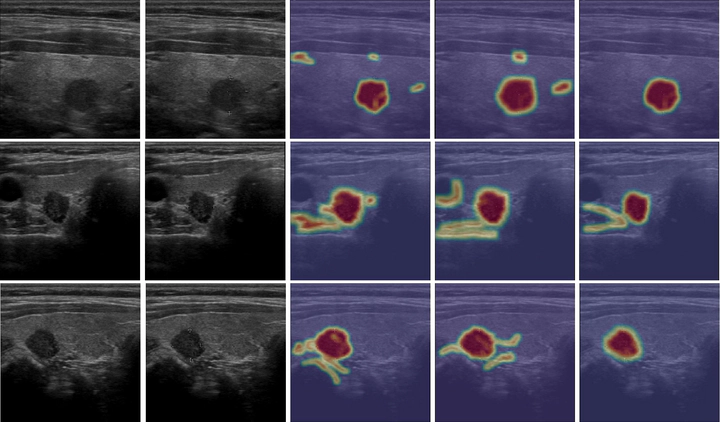

Computer-aided diagnosis (CAD) is becoming a prominent approach to assist clinicians spanning across multiple fields. These automated systems take advantage of various computer vision (CV) procedures, as well as artificial intelligence (AI) techniques, to formulate a diagnosis of a given image, e.g., computed tomography and ultrasound. Advances in both areas (CV and AI) are enabling ever increasing performances of CAD systems, which can ultimately avoid performing invasive procedures such as fine-needle aspiration. In this study, a novel end-to-end knowledge-driven classification framework is presented. The system focuses on multimodal data generated by thyroid ultrasonography, and acts as a CAD system by providing a thyroid nodule classification into the benign and malignant categories. Specifically, the proposed system leverages cues provided by an ensemble of experts to guide the learning phase of a densely connected convolutional network (DenseNet). The ensemble is composed by various networks pretrained on ImageNet, including AlexNet, ResNet, VGG, and others. The previously computed multimodal feature parameters are used to create ultrasonography domain experts via transfer learning, decreasing, moreover, the number of samples required for training. To validate the proposed method, extensive experiments were performed, providing detailed performances for both the experts ensemble and the knowledge-driven DenseNet. As demonstrated by the results, the proposed system achieves relevant performances in terms of qualitative metrics for the thyroid nodule classification task, thus resulting in a great asset when formulating a diagnosis.